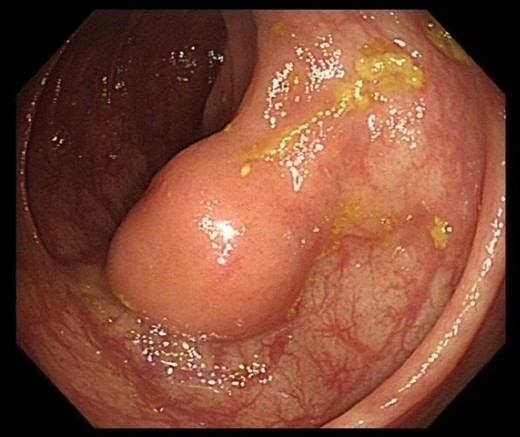

Previous colonoscopy, 4 years prior, had found several benign polyps. On recent colonoscopy, a 2 cm submucosal lesion within the ascending colon was identified and thought to be a lipoma (Figure Xa and Xb). Biopsies taken at the time were found to be benign with only oedematous large bowel mucosa seen, however these were superficial and no submucosal tissue was present (Figs 1–7).

Colonoscopy image of the ascending colon showing submucosal lesion.